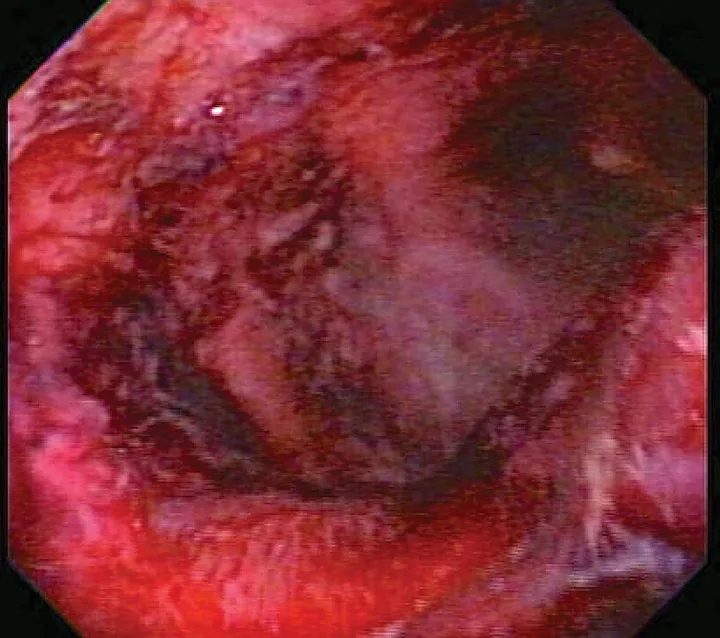

Critically ill patients are susceptible to GI ulceration (Figure 2) because of many factors, including primary or secondary GI disease, surgery, hypoperfusion, and mechanical ventilation. These patients also often require corticosteroids or NSAIDs because of inflammation, pain, and adrenal or immune-mediated disease. Ulceration can result in GI dysfunction, hemorrhage, and/or perforation.

FIGURE 2

Endoscopic image of duodenal ulcers in a critically ill patient